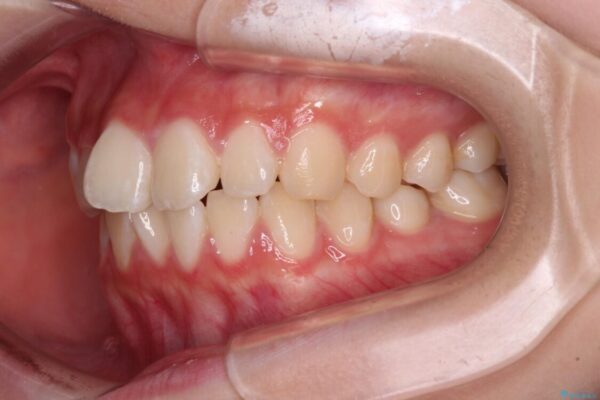

治療途中

• インビザラインは使える自信がない ワイヤー装置にて矯正治療 治療途中画像